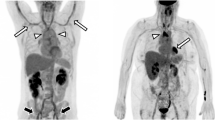

The image quality of [18F]FDG PET/MRI was rated in all cases as good (category 2) or excellent image quality (category 3). In [18F]FDG PET/CT, only a single scan was rated as diagnostic but image quality reduced (category 1) (see Table 3). This rating was based on multiple motion and breathing artefacts during CT acquisition. The analysis of diagnostic confidence in image quality showed no significant difference between the two groups. There were moderate interobserver agreements for [18F]FDG PET/MRI (κ = 0.366) and [18F]FDG PET/CT (κ = 0.578) for image quality. Figures 3 and 4 demonstrate representative [18F]FDG PET/CT and [18F]FDG PET/MR images from this study.

[18F]FDG PET/CT image showing an active aortitis with vessel wall thickening in sagittal reformatted CT angiography images (a) and [18F]FDG uptake at the aortic arch and the descending aorta (b). 3D volume rendering of the aorta shows no pathologic dilatation of the vessel (c). The tracer activity of 263MBq corresponding to 7.1 mSv and a DLP of 1625 mGy*cm corresponded to 24.375 mSv, and made up a total effective dose of 31.5 mSv

[18F]FDG PET/MR image of an inflammatory aortic aneurysm. Axial T1 vibe image after contrast shows the abdominal aortic aneurysm with vessel wall thickening and intraluminal thrombus formation (a). Fused images show pronounced [18F]FDG uptake within the thickened vessel wall as well (b, c). 3D rendering of the MR angiography shows the localized widening of the infrarenal aorta (d). The tracer activity of 289MBq corresponded to an effective dose of 7.8 mSv